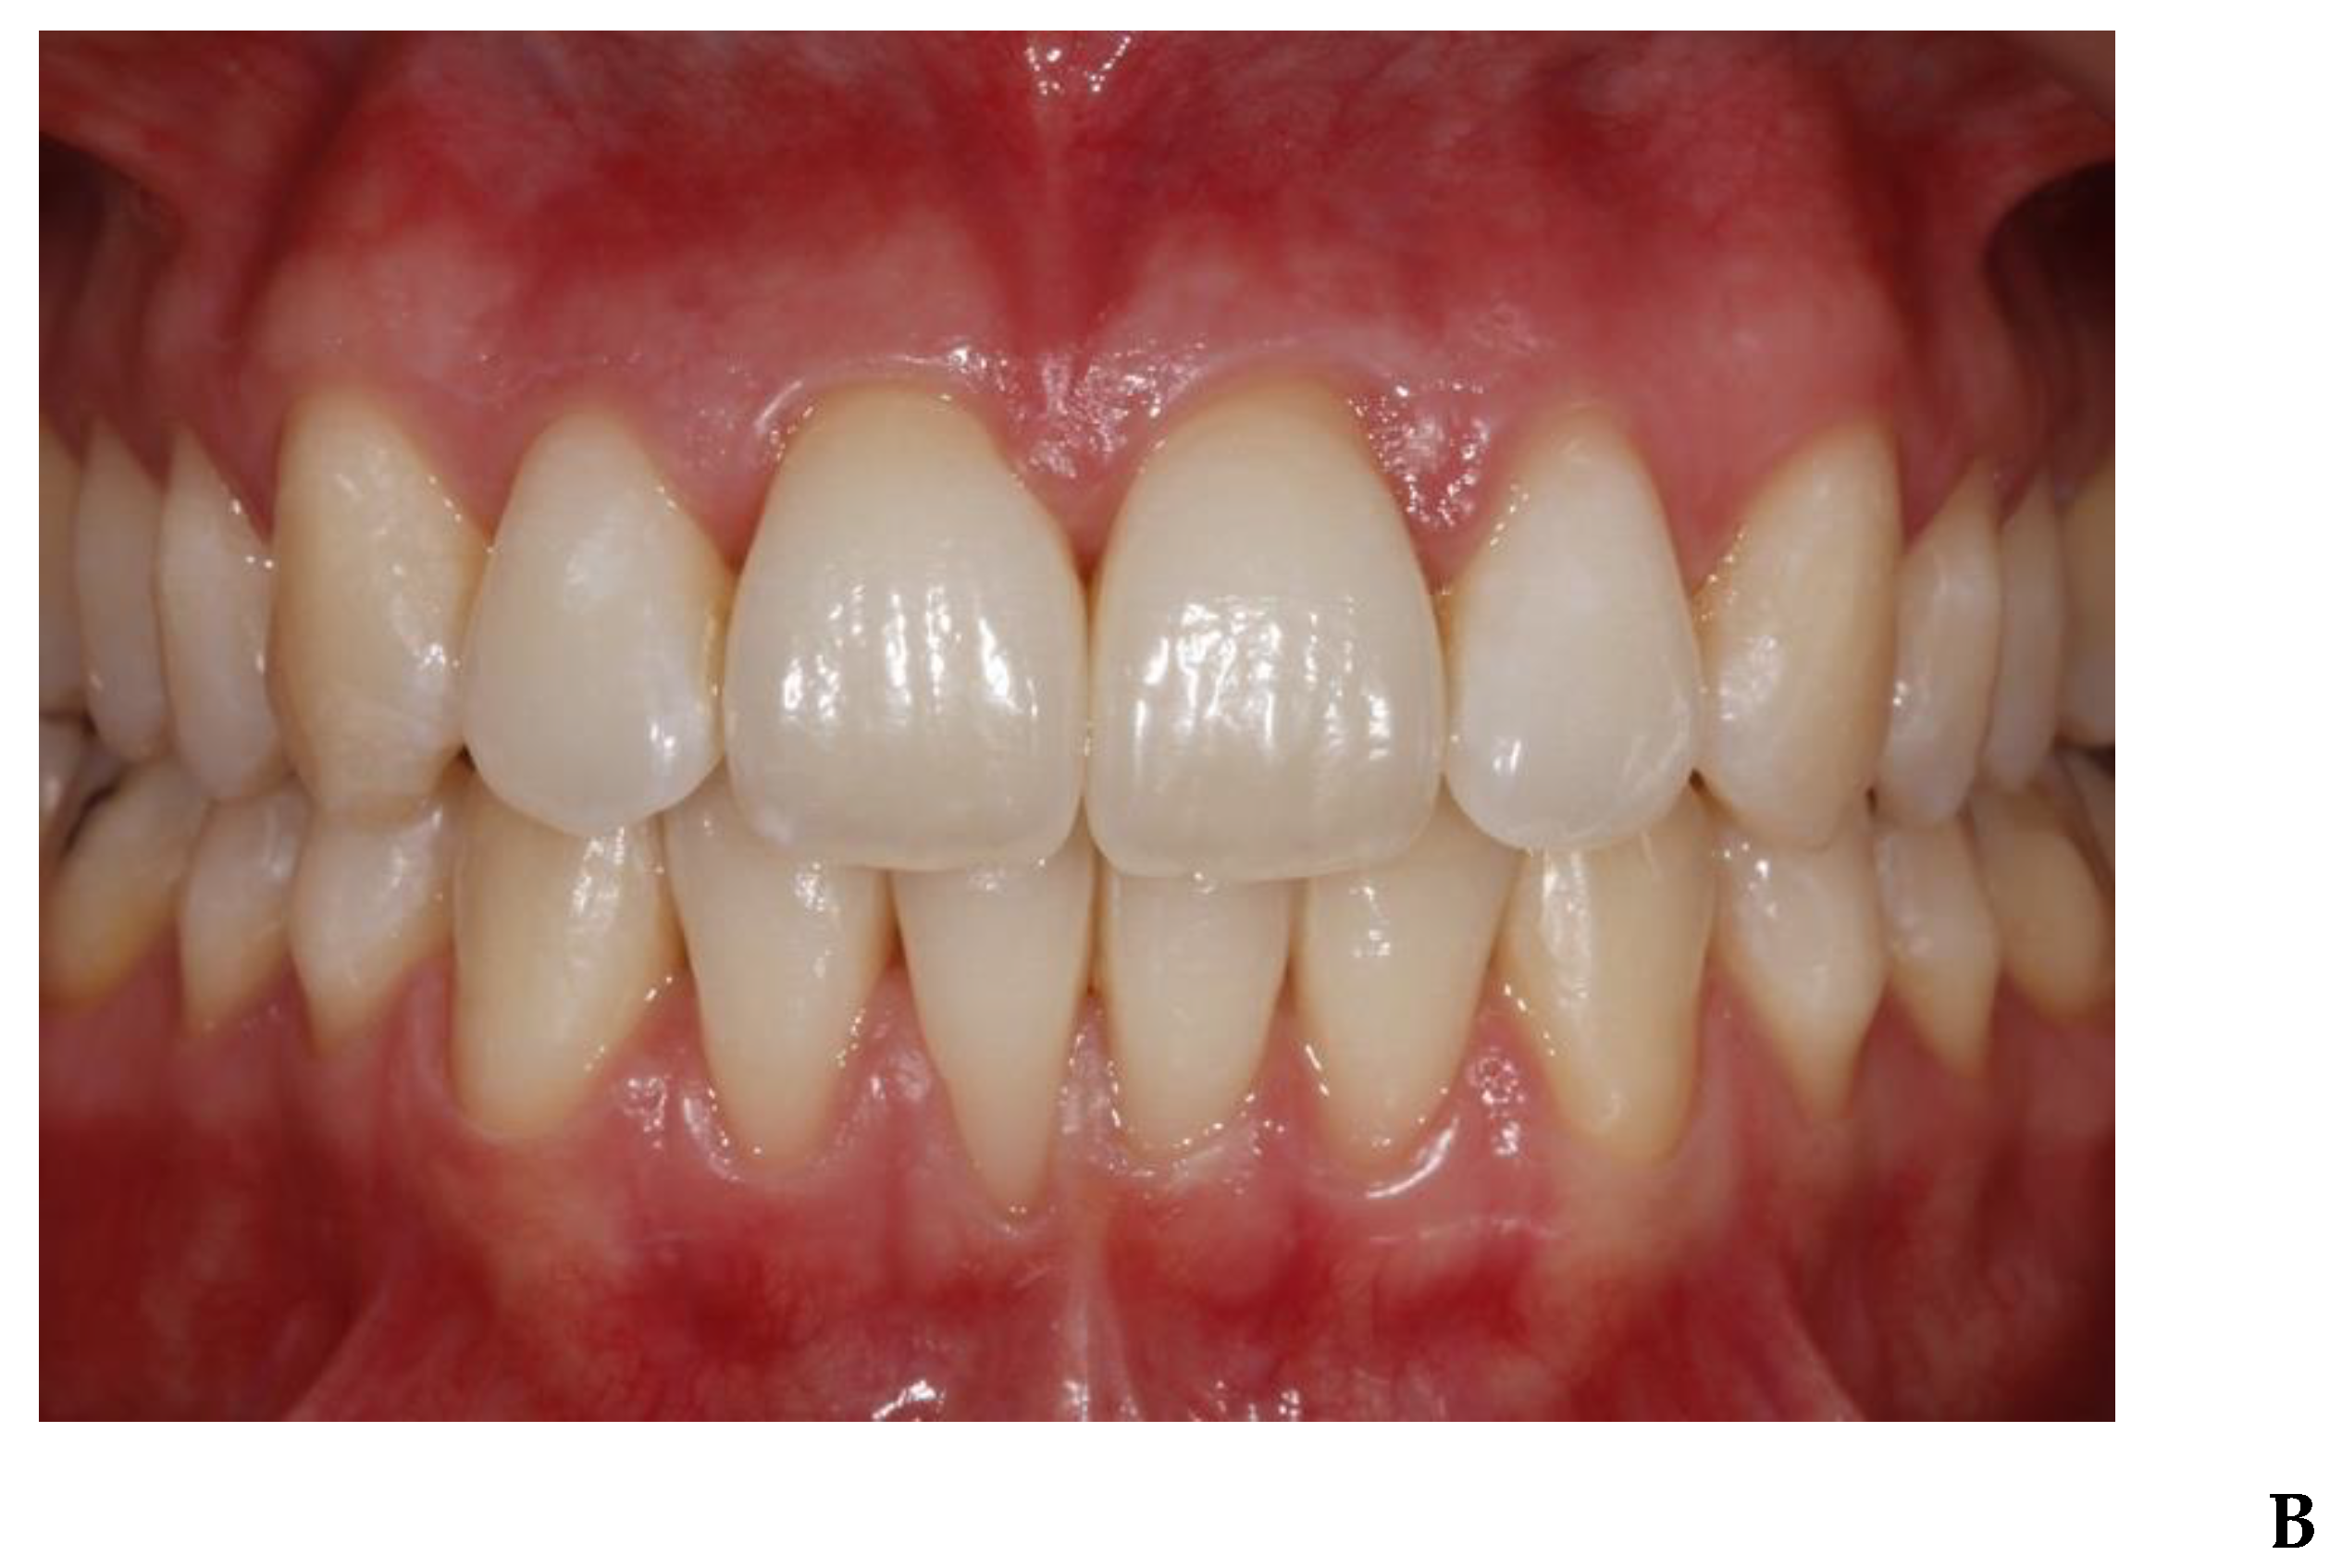

3. Results